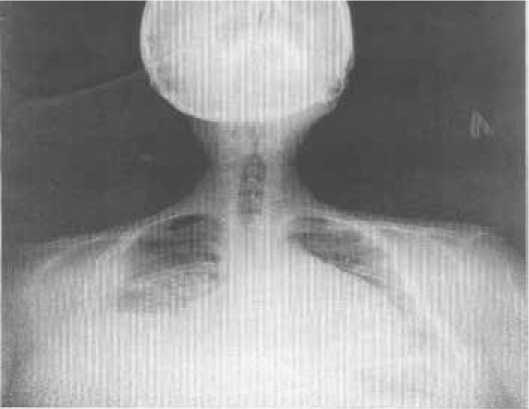

На рентгенограмме органов грудной клетки выраженный сколиоз грудной клетки, левосторонняя полисегментарная инфильтрация, выпот в правой плевральной полости и перикарде, увеличение левых камер сердца (рис. 3).

Рисунок 3. Рентгенограмма органов грудной клетки пациента Н. от 29.12.2015 г. [собственные данные]

Figure 3. Chest X-ray of patient N. from 29.12.2015[own data]